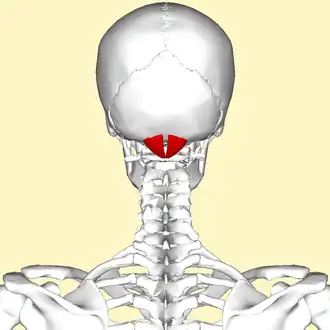

Human skull seen from back (rectus capitis posterior minor shown in red.) | |